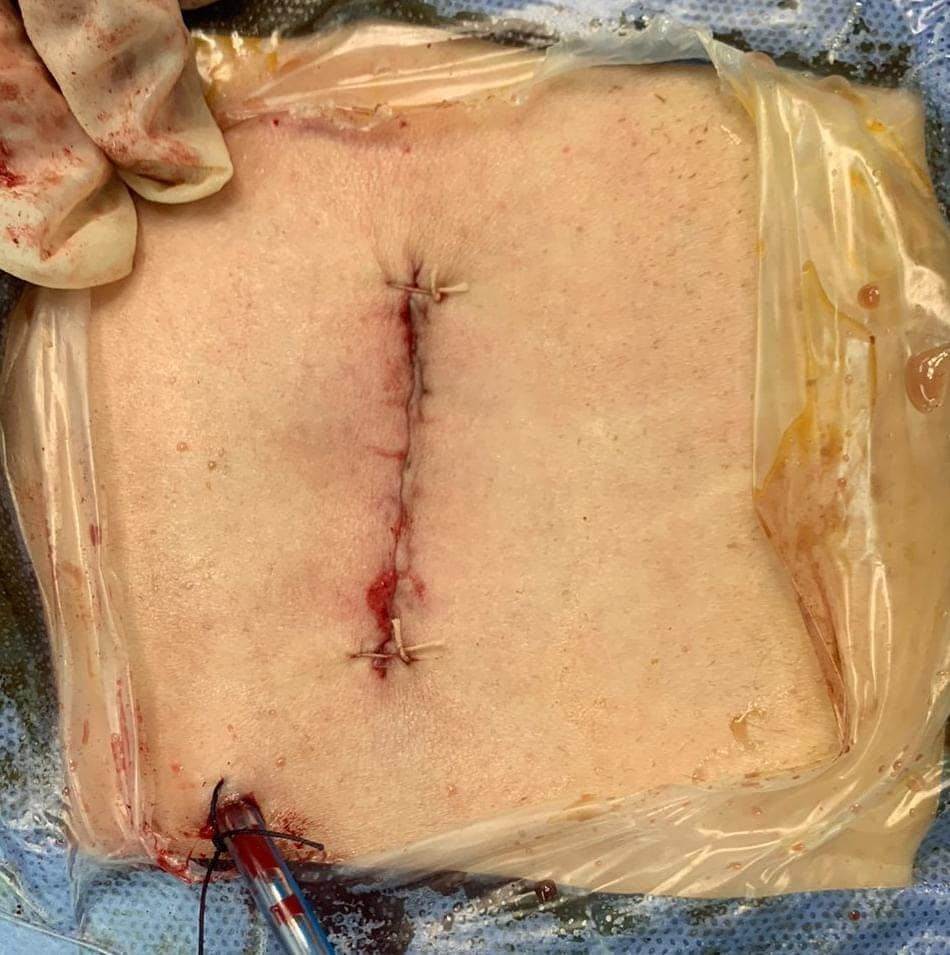

وقال الدكتور تامر حمدى أحمد مدير عام مستشفى بئر العبد التخصصى (في بيان) أنه تحت رعاية الدكتور خالد عبدالغفار وزير الصحة والدكتورة مها إبراهيم رئيس أمانة المراكز الطبية المتخصصة، والدكتور خالد الدرندلى رئيس جامعة الزقازيق والدكتور أحمد عنانى عميد كلية طب الزقازيق والدكتور محمود مصطفى طه رئيس قسم جراحة المخ والأعصاب بجامعة الزقازيق.. حيث قام الدكتور محمود محمد متولى مدرس مساعد جراحة المخ والأعصاب بجامعة الزقازيق بمساعدة الدكتور محمود الوكيل مدرس التخدير بالقصر العينى جامعة القاهرة باجراء جراحة لمريضة عمرها ٤٠عاما كانت تعانى من آلام شديدة وعرق نسا بالساق اليسرى تمنعها من المشى وممارسة حياتها اليومية بشكل طبيعى، وكانت لا تستجيب للعلاج، وأظهر الرنين المغناطيسى وجود انزلاق غضروفى ما بين الفقرات الخامسة القطنية والعجزية الأولى واختناق بجذور أعصاب الساق اليسرى، وقد تم تجهيز المريض ودخول العمليات واجراء جراحة لاستئصال الغضروف وتسليك جذور الأعصاب، وذلك من خلال جرح صغير بالظهر لا يتعدى الـ٣ سنتيمترات.

وأشار البيان الى أن هذا النوع من الجراحات فى غاية الدقة.. حيث يتم استئصال الغضروف وتسليك الأعصاب من جرح صغير بالجلد وفتحة صغيرة بالقناة الشوكية العظيمة دون التأثير على استقرار وثبات الفقرات ودون تثبيت للفقرات بشرايح ومسامير معدنية، وبواسطه تدخل محدود.